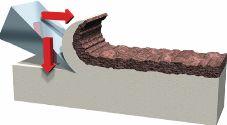

Los procedimientos de remoción de tejidos cariados con instrumentos de mano integran:

-

Tratamiento Restaurativo Atraumático -ART- (Frencken, J.E. 1994 9 - Holmgren, C. J. 1999 10) caracterizado por una eliminación mecánica del tejido reblandecido con instrumental de corte, afilado (hatchet, carver) (Figura 11).

-

Tratamiento químico de la dentina desnaturalizada y su posterior remoción con instrumental de mano no afilado, romo (Figura 12).

Fig. 12